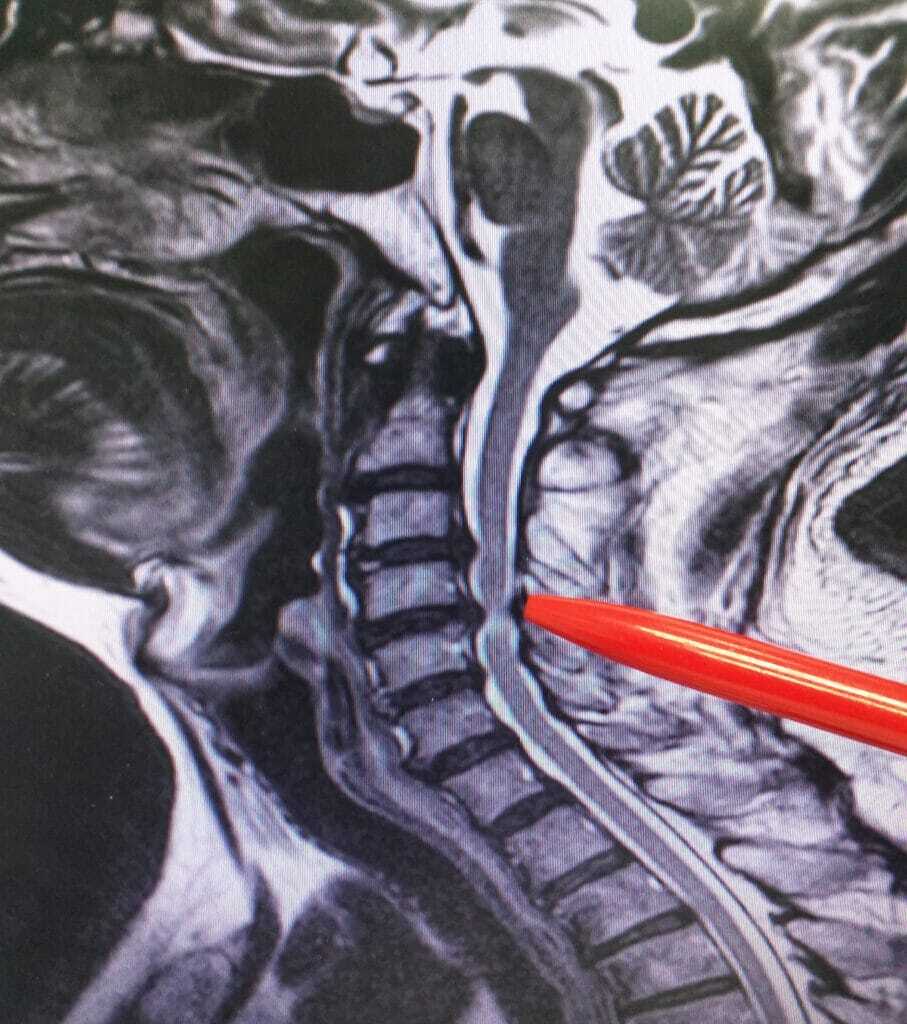

C1-C2 instability and a reverse curve

Of the many emails that I get are ones which discuss C1-C2 cervical spine instability. Many emails will talk about chronic upper cervical subluxation at C1-C2 and a reverse curve. The normal curve of the spine is shaped like a backwards “C.” If you have a problem with your neck, Lordosis is probably a word you are very familiar with. When your curve went from a natural “C” shape to a reverse curve you were probably told you had a reversed lordosis or your neck had become Kyphotic. Your neck is now curving in the opposite direction. This may be causing a lot of pain. Some of the pain maybe from muscle spasms. As the muscles are trying to stabilize the spine, the extra workload causes spasms.

When the spine is moving towards a reversed curve, adjacent segments may show cervical disc degeneration at lower levels such as C2-C3, C3-C4. These are the problems which will lead many people to a cervical spine fusion.